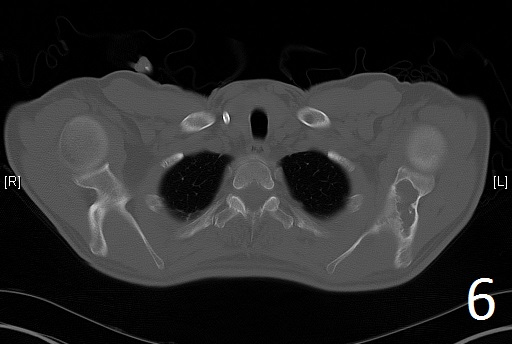

Fig. 6

Fig. 6-7. Axial CT reconstruction of the chest showing lytic and expansile lesion of the left scapula and ribs (polyostotic fibrous dysplasia).